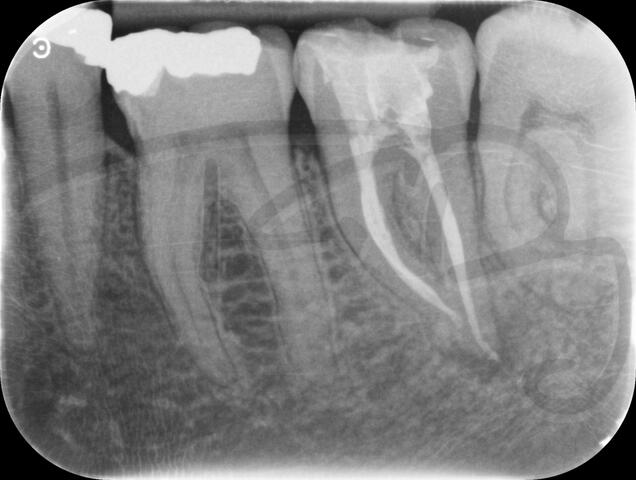

I am pleased to take endodontic referrals. Curved canals >30 degrees and potentially greater than 50 degrees can be negotiated. Sclerosed canals accessed. Post spaces prepared and the patient returned to you ready to restore.In most cases existing crowns, bridges and veneers can be retained with the endodontic access aesthetically restored after the full canal network has been treated.In the first instance I would prefer a radiograph and a brief list of patient expectations and a tooth history.

There are a number of ways to decide whether you need root canal treatment and the specific x-rays, scans and tests help diagnose your problem.An important sign is the type of pain you have been having with a tooth. It helps me decide if a tooth is in need of treatment and even if it saveable.

I really enjoy undertaking root canal treatments - rising to the challenge and helping people out of dental pain for the long term.I was privileged to be asked to speak at the 2016 BDA Conference, where I have a lecture about providing quality endodontic outcomes to patients, working as a generalist. Avoiding problems and pitfalls and maximising efficiency. One of the main matters that he covered was understanding that what is seen on plane radiography is utterly misleading and should not be the criteria by which a generalist continues treatment once it has been started.

At the 2016 BDA Conference, Thomas spoke about providing quality endodontic outcomes to patients, working as a generalist. Avoiding problems and pitfalls and maximising efficiency. One of the main matters that he covered was understanding that what is seen on plane radiography is utterly misleading and should not be the criteria by which a generalist continues treatment once it has been

started.